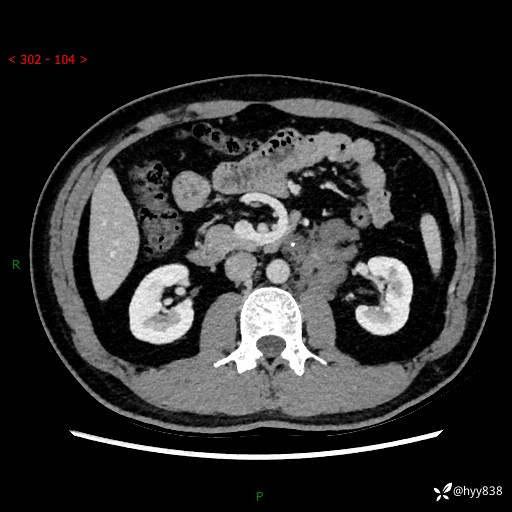

现病史:患者3月余前检查发现左侧腹膜后占位,大小约3.7*4.9cm,平素无腰疼,无肉眼血尿,无尿频尿急等不适,当时未特殊处理,在门诊复查CT提示左侧腹膜后占位,门诊拟“左侧腹膜后占位”收入院。 起病以来,患者精神佳,饮食、睡眠良好,大小便正常,体力体重无明显变化。

腹膜后CT平扫+增强